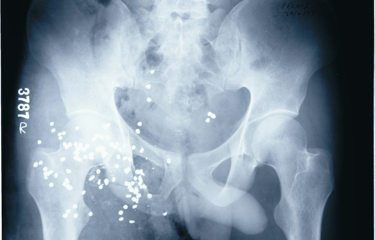

Lead pallets are seen in the pelvic region